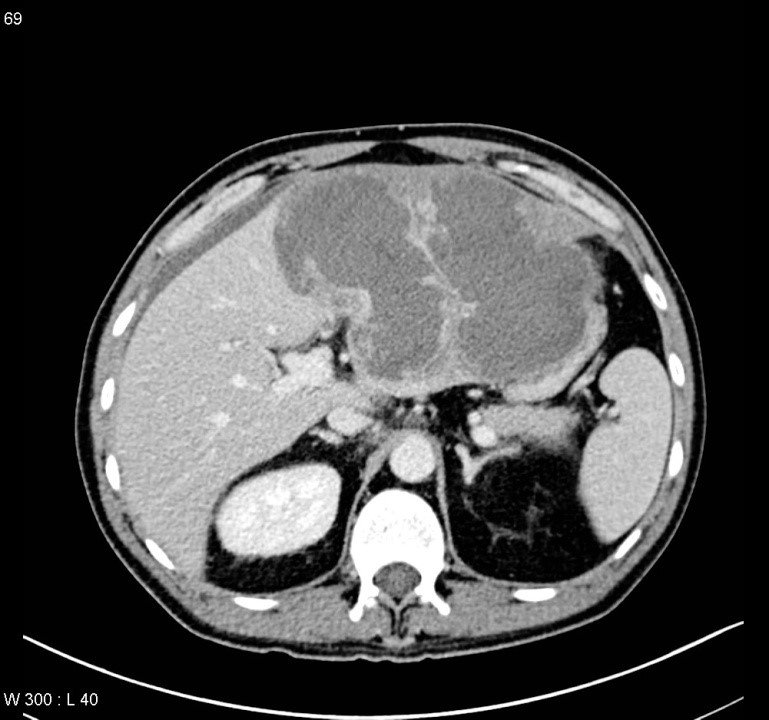

- Görüntüləmədə I seqment hipertrofiyası (yüksək şübhə əlaməti)

- Diaqnozu dəqiqləşdirmək üçün Qc venaları yoxlanılmalıdır. Bunun üçün dopler USM, KT-angioqrafiya, MRT-angioqrafiyalar və ya kontrastlı venoqrafiya edilir.

- Görüntüləmədə Qc venalarının trombotik tutulması diaqnozu dəqiqləşdirən əlamətdir.

- Görüntüləmədə qaraciyər venalarının tıxanması

PVT diaqnozunu dəqiqləşdirmək üçün portoqrafiya aparılır – Doppler USM, KT və ya MRT angioqrafiya.

- Kontrastlı müayinələrdə damarda tromb və ya kavernoz transformasiya

Baddi-Kiari sindromu böyük qaraciyər venalarının tıxanması nəticəsində meydana gələn venoz durğunluqdur, qaraciyər venaları ilə yanaşı aşağı boş venada da tıxanma ola bilir. Tromboz, fibroz, membran və infiltrasiya (şişlər, iltihab) ən çox rast gələn səbəbləridr. Erkən mərhələlərdə kəskin hepatit və kəskin qaraciyər yetməzliyi, xroniki mərhələdə sirroz və PH meydana gələ bilir. Diaqnozu üçün tomoqrafiya və kontrastlı angioqrafiya lazım gəlir, Qc venalarının trombotik tutulması diaqnozu təsdiqləyir. digər xarakterik əlaməti birinci seqmentin hipertrofiyasıdır. Erkən mərhələdə dekompressiya (cərrahi və stend) sirroz əmələ gəldikdə isə transplantasiya ön planda tutulur.

Qaraciyər venalarının görünməməsi, kontrastlaşmaması və ya trombla tıxanması.

- Görüntüləmədə qaraciyər venalarının tıxanması, I seqment hipertrofiyası ola bilər (xroniki forma);

- portoqrafiyada vena mənfəzində trombun görünməsi;

- venanın distalında genişlənmə və kavernoz transformasiyanın görünməsi;